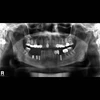

Diş hekimi